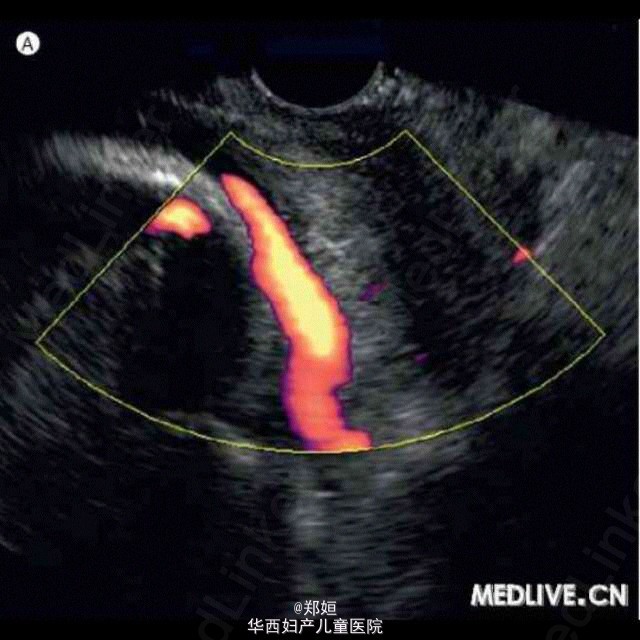

病历资料:女,25岁,G1P0,孕龄33周。超声检查显示出胎盘基底及脐带插入胎盘表面,但脐带插入部位不能显示。由于患者报告阴道有异物流出,因此行阴道内超声检查。多普勒超声检查显示,胎儿血管位于宫颈内口之上, 符合胎盘前置的诊断。子宫分娩力检测仪证实存在频繁的宫缩。给予倍他米松以促成胎儿肺成熟。考虑到生产中可能会有脐带血管系统受损和破裂的风险,因此选择剖宫产以终止妊娠。产妇娩出重2115 g的健康男婴。娩出的胎盘标本符合帆状胎盘的诊断,胎儿脐血管位于宫颈内口之上提示为胎盘前置。随访,该产妇与婴儿健康状况良好。 柳叶刀中文版